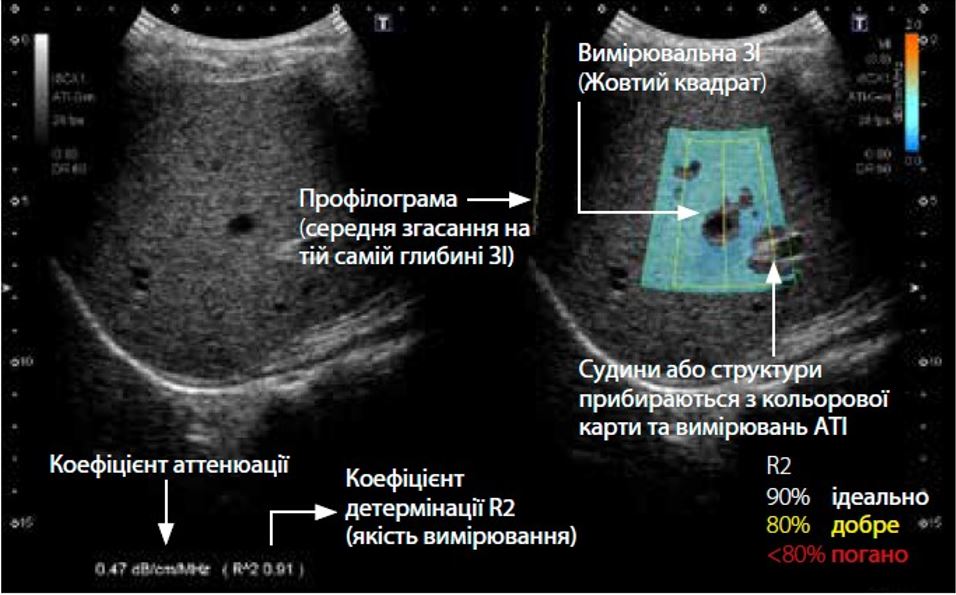

Малюнок 1 Принцип роботи атенюації (ATI)

Характеристики ATI можна переглянути на зображенні з вимірюванням ATI (рис. 2). Рівень затухання позначається кольором і відображається в ROI. Області зі значними помилками обчислення затухання, такі як структури (кровоносні судини) або області з сильними артефактами (реверберація), виключаються на карті ATI. Оскільки відображаються лише надійні області для вимірювання, точне вимірювання ATI можна отримати швидко та легко. Крім того, коефіцієнт визначення (детермінації) відображається разом із коефіцієнтом затухання, що дозволяє клініцистам підтвердити оптимальне розташування для розміщення досліджуваної ділянки з метою підвищення точності.

Малюнок 2 Особливості вимірювання атенюації

CAP: 165 dB/m (0.47 dB/cm/MHz), ATI: 0.43 dB/cm/MHz